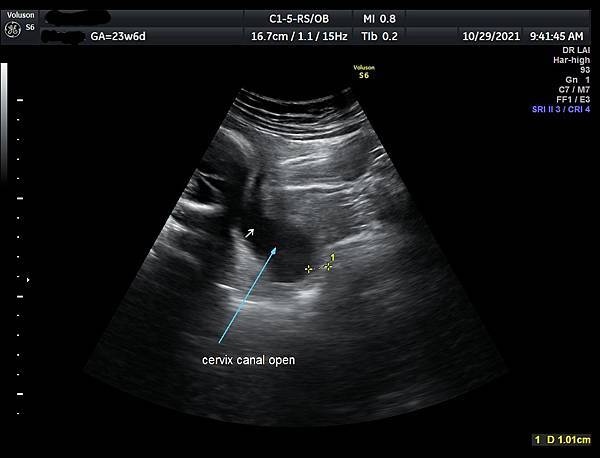

▲top

• 孕兒診所賴錫鉅醫師 341 預防早產需要量測子宮頸長度 : 孕期性行為要戴保險套

預防早產需要量測子宮頸長度

孕期性行為要戴保險套